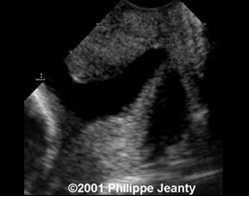

- Siêu âm bìu:

- Các bất thường của tinh hoàn như: nang mào tinh, tràn dịch tinh mạc, giãn tĩnh mạch thừng tinh, sỏi nhỏ tinh hoàn.

Đặc điểm siêu âm bìu

Bảng 4. Các đặc điểm siêu âm bìu

Trong các bất thường ở bìu được phát hiện qua siêu âm, giãn tĩnh mạch thừng tinh chiếm tỉ lệ cao nhất: 36,4%.